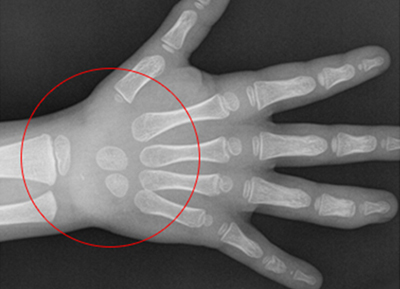

손으로 확인하는

우리아이 성장판 검사

아이의 나이 만으로 발육 정도를 파악 할 수 있지만 동일한 나이임에도 불구하고

개인적인 성숙도가 많이 다르기 때문에 정확한 성장 정도를 판단하기 위해 성정판 검사를 통해 교정의 적절한 시기를 결정합니다.

• 1

열려있는 성장판

• 2

닫혀가는 성장판

• 3

완전히 닫힌 성장판

성장판이 닫혀 있어도 치아 교정이 가능하지만 골격적인 부분에 대한

교정이 이루어 지려면 성장판이 닫히기 전에 교정을 시작하여야 더 좋은 효과를 기대할 수 있습니다.